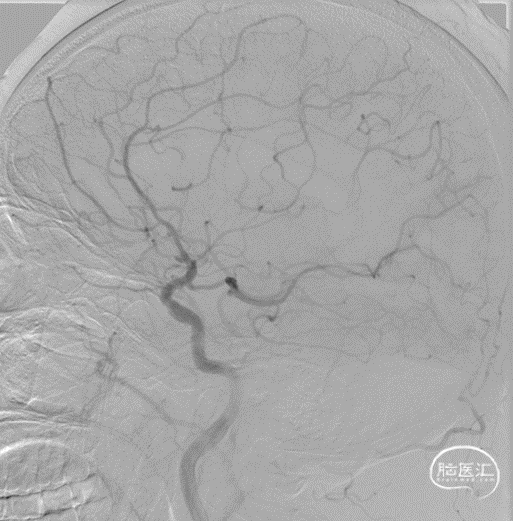

最后工作位造影和正侧位造影,右侧大脑中动脉区域血流恢复,灌注满意。

术后CT无出血,术后患者未诉不适,无新发神经功能症状及体征,继续予以抗栓、强化降脂、调节血糖等治疗。